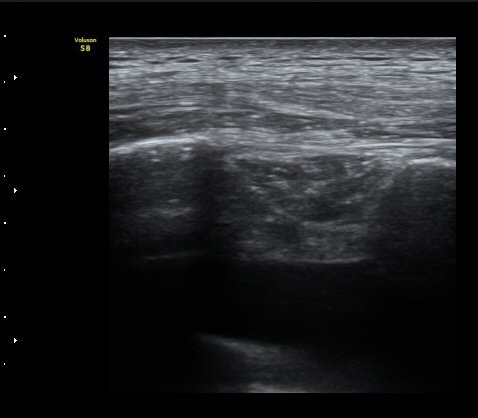

°¥ºñ»À ÇÇÁú°ñ ¿¬°á¼º ¼Ò½Ç°ú ¾à°£ÀÇ ÀüÀ§, ¿¬ºÎÁ¶Á÷ ºÎÁ¾ÀÌ °üÂûµÊ (loss of cortical continuity and soft tissue swelling of rib)  »çÁø 2